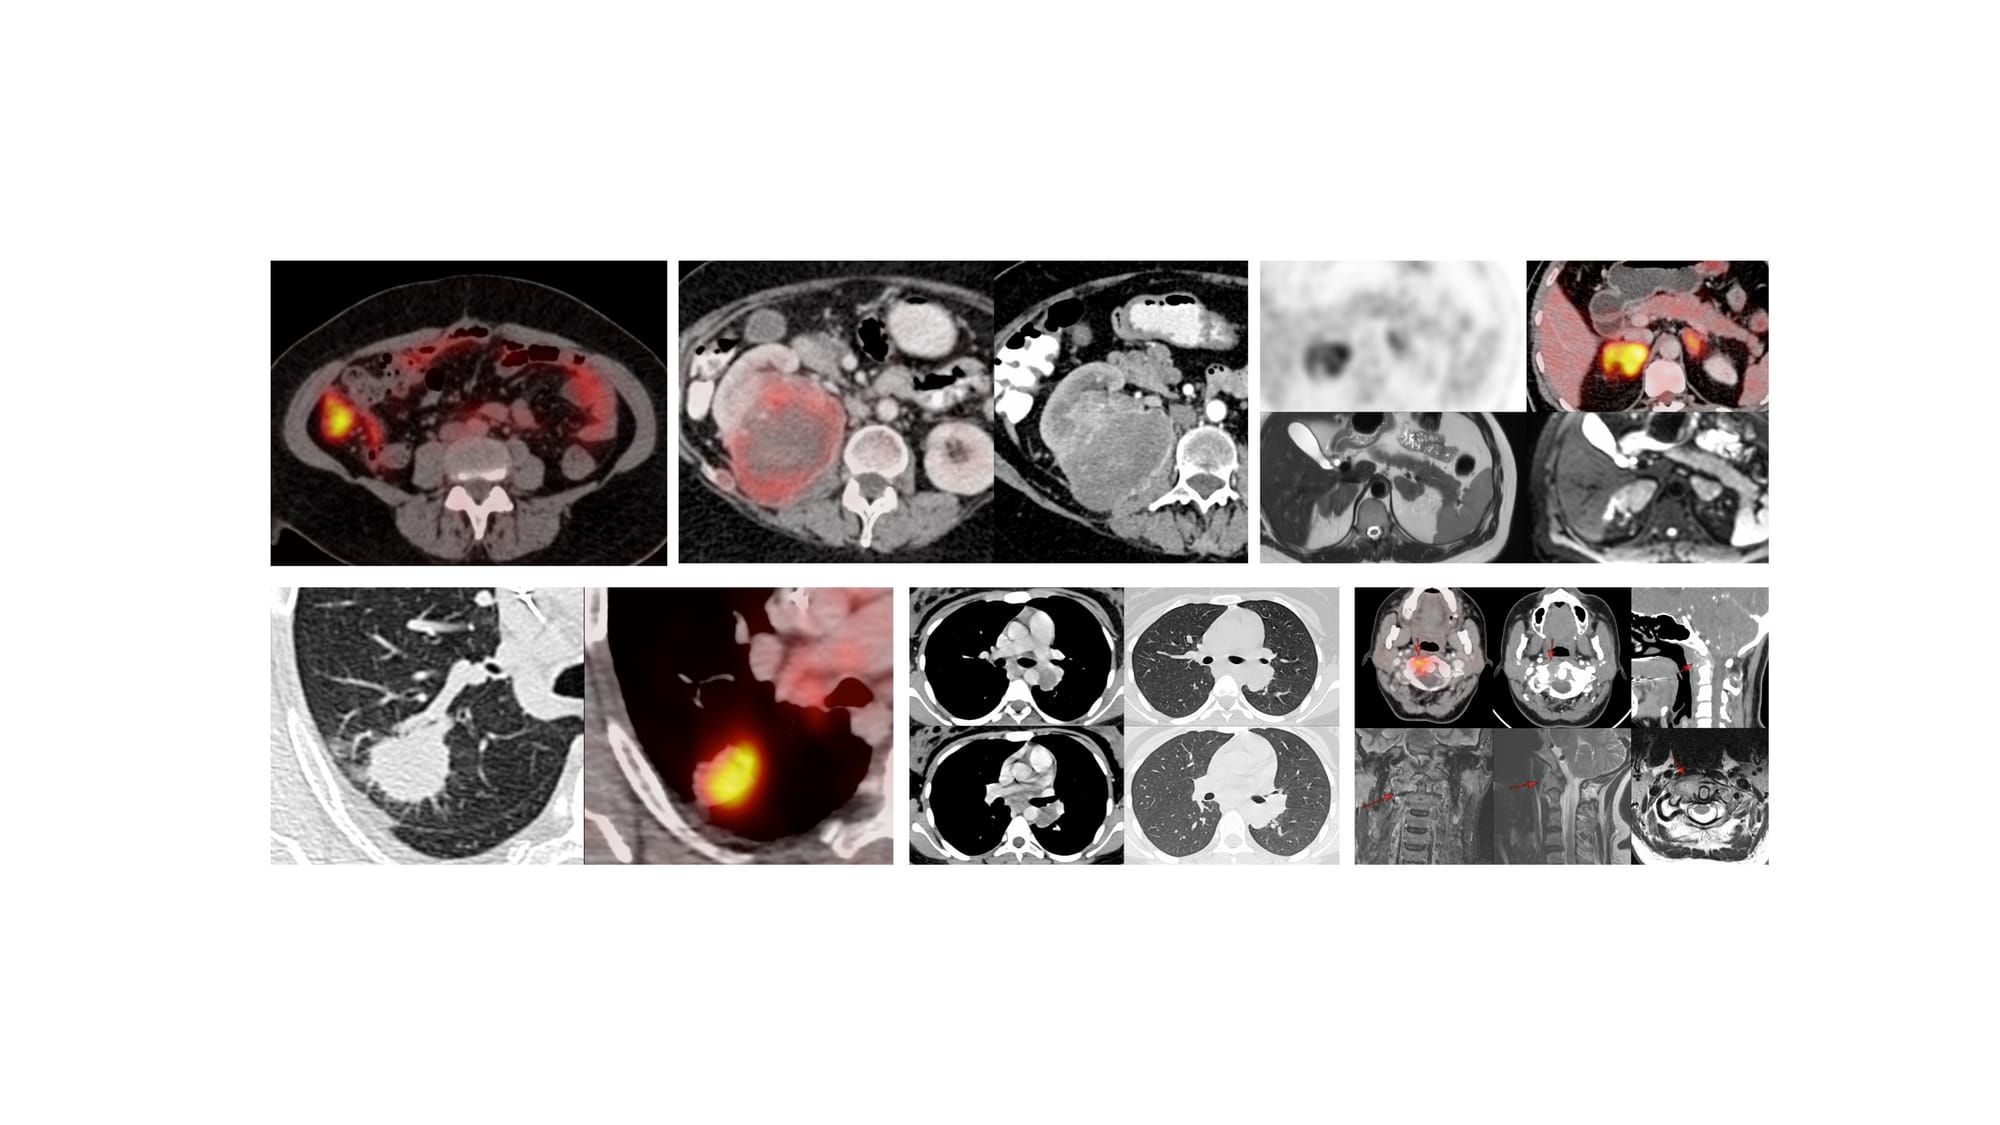

The 7 Cases for YouTube Live on 08 Jan at 7 PM Indian Standard Time